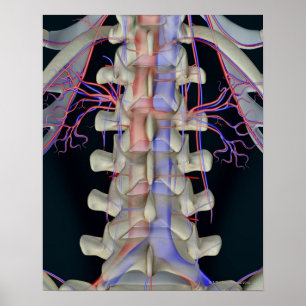

Blodtillförsel av ländkotor vykort

Pris21,00 kr

Blodtillförsel av ländkotor poster

Pris297,00 kr